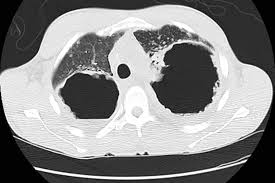

Can Lung Cancer Be Mistaken For Sarcoidosis - Case Report Pulmonary And Liver Sarcoidosis F1000research - Researchers emphasize that clinicians should be aware of systemic sarcoidosis because it can easily be mistaken for cancer progression.. Therefore we suggest that no lesion should be missed in these patients without biopsy by assuming lung involvement of sarcoidosis. Lung cancer should be excluded to confirm a diagnosis of sarcoidosis 4 , although the concurrence of sarcoidosis and lung cancer has been reported 5, 6, 7, 8 . Sarcoidosis patients may be misdiagnosed with tuberculosis, lymphoma, or lung cancer 4 . The standardized mortality rate for lung cancer was 3.26 (5.56 for males and 3.03 for females), indicating that sarcoidosis could be a risk factor for lung cancer. Various organs can be affected including the skin, lymph nodes, and liver.

Sarcoidosis is a rare disease caused by inflammation. These lumps are called granulomas and can affect how the lungs work. Furthermore, lung cancer symptoms, such as a persistent cough, back pain or weight loss, can resemble a cold or bronchitis and may not raise suspicions of lung cancer, herrera adds. 53 patients were found to have cancer after their sarcoid diagnosis of whom 27 were male (51%) and 26 were female (49%). There are currently no formal recommendations to guide the differential diagnosis workup between the evolution of lymphoma or a solid cancer and a granulomatous reaction associated with neoplasia.

When sarcoidosis affects the lungs, symptoms can mimic idiopathic pulmonary fibrosis including shortness of breath and a dry cough. Because both mesothelioma and sarcoidosis are hard to detect and present generalized chest and respiratory symptoms, the two conditions can be mistaken for one another. By definition, sarcoidosis is a systemic disease, affecting multiple organs in the body. If it is sarcoid, then you can get the help you need for this condition. There are currently no formal recommendations to guide the differential diagnosis workup between the evolution of lymphoma or a solid cancer and a granulomatous reaction associated with neoplasia. Since sarcoidosis and lung cancer can be present concurrently, performing biopsy to obtain pathology results from any suspected lung lesion in a patient diagnosed with sarcoidosis is essential. What every physician needs to know. Sarcoidosis is known to be a cancer mimicking and masking condition, it can follow cancer or develop concurrently with cancer, and significantly increased risk of cancer can affect sufferers of sarcoidosis.

Pancreatic cancer may be diagnosed as diabetes, due to the fact that diabetes is often a symptom or risk factor of pancreatic cancer. One report notes a case of systemic sarcoidosis that mimicked the symptoms and metastatic spread of cancer. Since sarcoidosis and lung cancer can be present concurrently, performing biopsy to obtain pathology results from any suspected lung lesion in a patient diagnosed with sarcoidosis is essential. When referring to the stages of sarcoidosis, this is referring exclusively to pulmonary sarcoidosis. Sarcoidosis is known to be a cancer mimicking and masking condition, it can follow cancer or develop concurrently with cancer, and significantly increased risk of cancer can affect sufferers of sarcoidosis. Although it is most commonly thought to be a lung disease, sarcoidosis has been shown to affect almost any organ. There are currently no formal recommendations to guide the differential diagnosis workup between the evolution of lymphoma or a solid cancer and a granulomatous reaction associated with neoplasia. Apparently, lymphomas can sometimes harbor sarcoidal granulomas within cancer — and this change, although rare, is thought to perhaps reflect an immune reaction to the cancer tumor, and not the systemic disease, sarcoidosis.